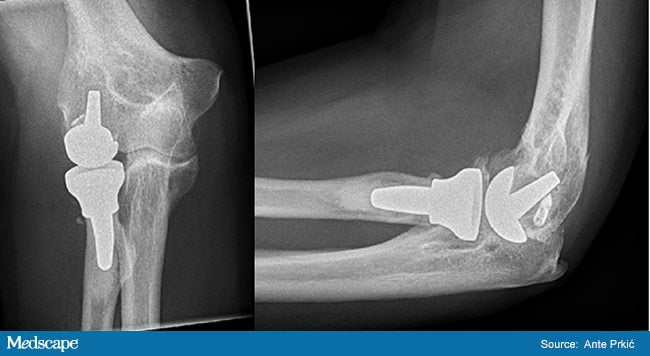

При неэффективности консервативного лечения, быстром прогрессировании артрита, развитии осложнений показано хирургическое вмешательство. Это синовэктомия, артротомия, резекция локтевого сустава, хейлэктомия, артроскопия. Пациентам с остеоартритом 3 степени тяжести врачи сразу предлагают установку эндопротеза, так как консервативное лечение при выраженной деформации костей не имеет смысла.

Эндопротезирование локтевого сустава

Установка искусственного сустава проводится под эндотрахеальным наркозом. Хирург делает разрез на задней поверхности локтя, отделяет и закрепляет нерв, рассекает фасции, сухожилия. После удаления локтевого отростка устанавливает имплантат, закрепляет его цементным или бесцементным способом.

Затем хирург фиксирует локтевой нерв в отдельном канале, сшивает мягкие ткани. Реабилитация начинается спустя 1-2 дня. Срок службы эндопротеза — 10-15 лет.